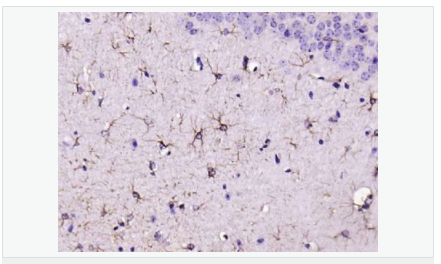

| 产品应用 | WB=1:500-2000 ELISA=1:5000-10000 IHC-P=1:200-1000 IHC-F=1:200-1000 Flow-Cyt=1μg/Test ICC=1:100 IF=1:200-800 (石蜡切片需做抗原修复) not yet tested in other applications. optimal dilutions/concentrations should be determined by the end user. |

| 产品介绍 | This gene encodes one of the major intermediate filament proteins of mature astrocytes. It is used as a marker to distinguish astrocytes from other glial cells during development. Mutations in this gene cause Alexander disease, a rare disorder of astrocytes in the central nervous system. Alternative splicing results in multiple transcript variants encoding distinct isoforms. [provided by RefSeq, Oct 2008] Function: GFAP, a class-III intermediate filament, is a cell-specific marker that, during the development of the central nervous system, distinguishes astrocytes from other glial cells. Subunit: Interacts with SYNM. Isoform 3 interacts with PSEN1 (via N-terminus). Subcellular Location: Cytoplasm. Note=Associated with intermediate filaments. Tissue Specificity: Expressed in cells lacking fibronectin. Post-translational modifications: Phosphorylated by PKN1. DISEASE: Defects in GFAP are a cause of Alexander disease (ALEXD) [MIM:203450]. Alexander disease is a rare disorder of the central nervous system. It is a progressive leukoencephalopathy whose hallmark is the widespread accumulation of Rosenthal fibers which are cytoplasmic inclusions in astrocytes. The most common form affects infants and young children, and is characterized by progressive failure of central myelination, usually leading to death usually within the first decade. Infants with Alexander disease develop a leukoencephalopathy with macrocephaly, seizures, and psychomotor retardation. Patients with juvenile or adult forms typically experience ataxia, bulbar signs and spasticity, and a more slowly progressive course. Similarity: Belongs to the intermediate filament family. SWISS: P14136 Gene ID: 2670 Database links: Entrez Gene: 2670 Human Entrez Gene: 14580 Mouse Omim: 137780 Human SwissProt: P14136 Human SwissProt: P03995 Mouse Important Note: This product as supplied is intended for research use only, not for use in human, therapeutic or diagnostic applications. 星形胶质细胞标志物 (Astrocyte Marker) GFAP是一个56kDa的中间丝蛋白(intermediate filament,IF),在中枢神经系统发育期是一个特异性的标志物,以区别星形细胞和其它胶质细胞。GFAP表达在皮层和海马,急、慢性皮质酮治疗时表达减少。 GFAP可以和人、大鼠、小鼠的GFAP反应,在正常和肿瘤性的星形胶质细胞阳性表达,而神经节细胞、神经元、成纤维细胞、少突胶质细胞和这些细胞来源的肿瘤细胞阴性表达,主要用于星形胶质瘤等中枢神经系统肿瘤的诊断和鉴别诊断,GFAP的缺乏可导致AD病。 |